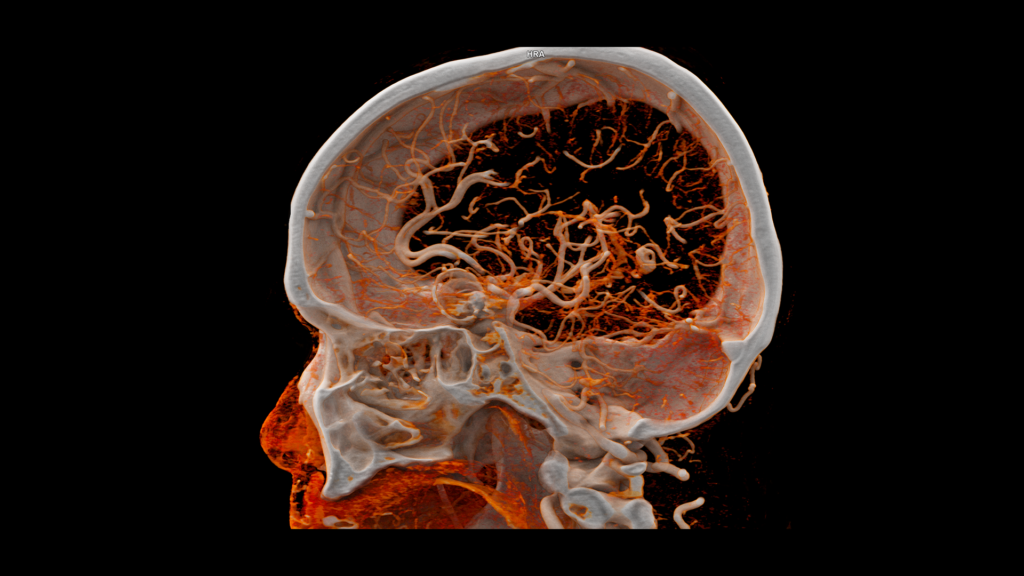

Photon-counting CT in neurologia

Il miglioramento del contrasto delle immagini e la maggiore risoluzione spaziale possono aumentare l’affidabilità della valutazione di piccoli dettagli anatomici, anche nei vasi sanguigni cerebrali di dimensioni minori.